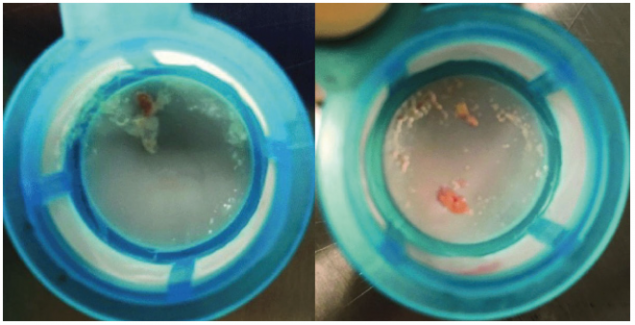

・ほぼ全ての症例(99%)でいずれかのフィルタにデブリス

(弁尖や石灰化病変の組織片、心筋筋組織、血栓塊 等)が捕捉

・手技中の血管アクセスに関連する合併症の発生率は0.4%※2